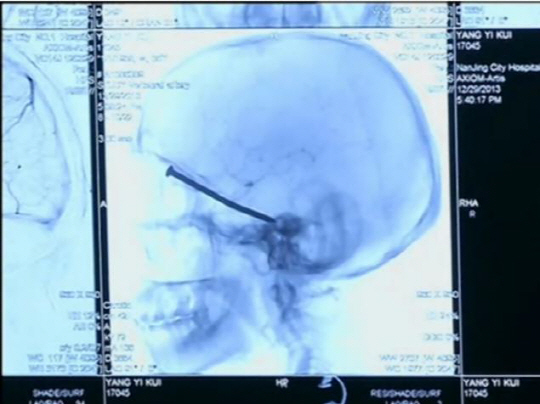

중국 남성이 길이 8cm짜리 대못이 뇌 속에 박히는 사고를 당했지만 기적적으로 생존해 화제다.

당시 그는 왼쪽 눈으로 이물질이 날아들어온 듯한 느낌을 받았으며, 약간의 통증과 함께 피가 났지만 대수롭지 않게 여겼다는 것이다.

그는 다음날 잠에서 깨자 눈쪽이 심하게 붓고 두통을 느끼다가 병원을 찾았다.

담당의사는 "대못이 박힌 부근에는 시신경을 비롯해 주요 혈관 등이 자리하고 있어 실명 또는 생명이 위태로울 수 있었다"며 "그나마 운이 좋았다"고 말했다. 현재 양씨는 시신경 등 손상없이 병원에서 회복중이다.